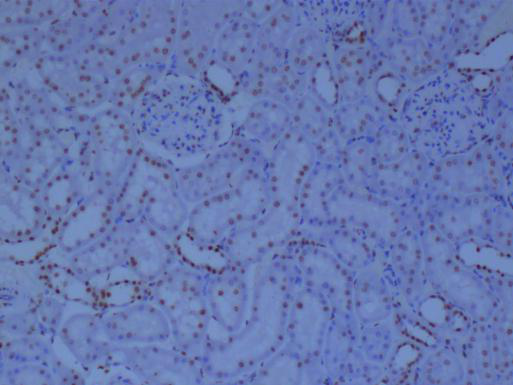

冰凍切片實(shí)驗(yàn)是生物學(xué)、醫(yī)學(xué)等領(lǐng)域中常用的一種實(shí)驗(yàn)技術(shù),主要用于觀察和研究生物組織的微觀結(jié)構(gòu)。在進(jìn)行冰凍切片實(shí)驗(yàn)時(shí),掌握一些關(guān)鍵的技巧對(duì)于獲得高質(zhì)量的切片至關(guān)重要。本文將詳細(xì)分享一些冰凍切片實(shí)驗(yàn)的技巧,幫助讀者更好地進(jìn)行實(shí)驗(yàn)。